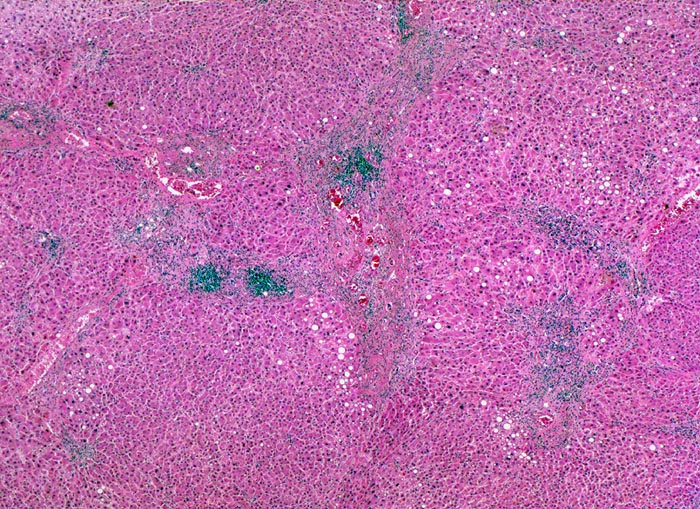

chronische Hepatitis C mit minimaler Aktivität

Der Verlauf der Portalfelder ist an dichten lymphoiden Entzündungsinfiltraten erkennbar, welche zum Teil gebogen verlaufen. Dieser Verlauf deutet auf eine portoportale fibröse Septenbildung hin. Ein vollständiger zirrhotischer Umbau mit Knotenbildung liegt noch nicht vor.

Das Ausmass der Fibrose wird bei chronischen viralen Hepatitiden als Staging angegeben. Dieses reicht von einer leichten Bindegewebsvermehrung in den Portalfeldern über eine portoportale Septenbildung und einen unvollständigen zirrhotischen Umbau bis zur voll etablierten Zirrhose. Es existieren verschiedene Grading- und Staging Systeme für die Bestimmung des Schweregrades einer chronischen viralen Hepatitis. Vor allem das Ausmass der Fibrose ist entscheidend für die Therapieindikation.